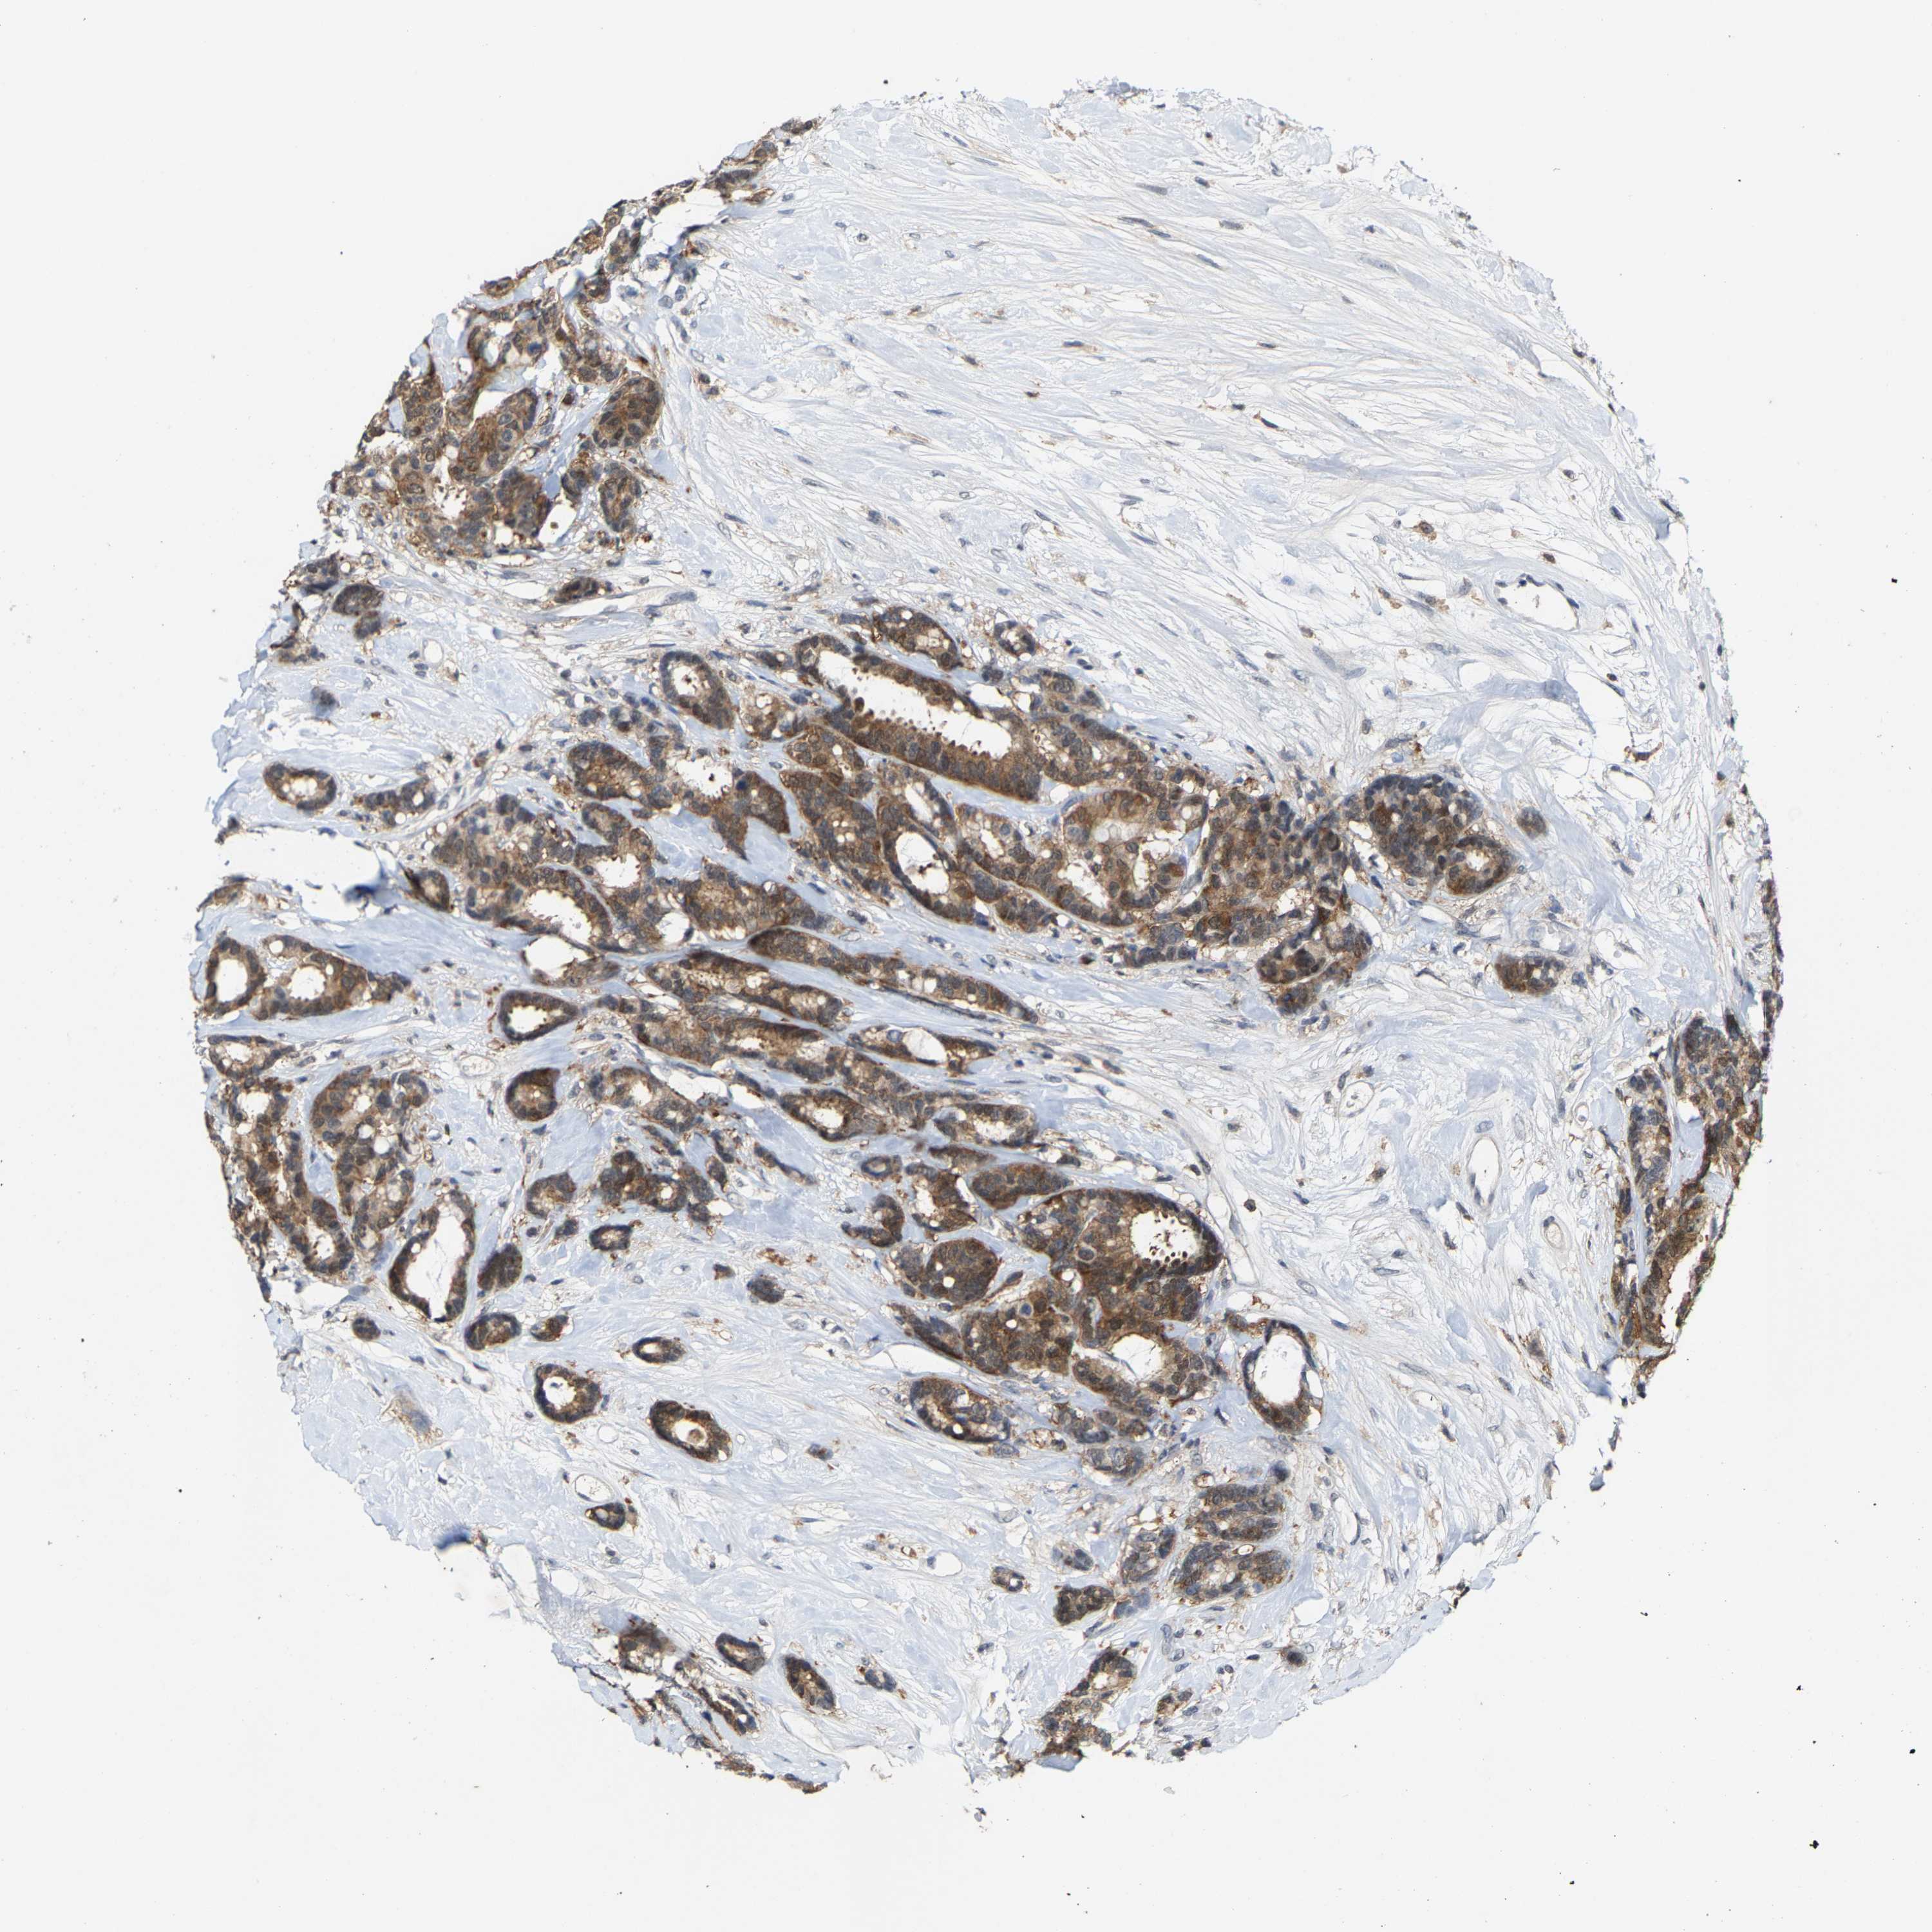

CANCER BREAST CANCER Show tissue menu

BRCA TCGA BRCA VALIDATION PROTEIN EXPRESSION